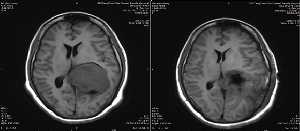

神經(jīng)外二科成功實施側(cè)腦室三角區(qū)巨大腦膜瘤全切術(shù)

8月2日,以續(xù)繼軍主任為首的神經(jīng)外二科團隊,精心設(shè)計手術(shù)方案以及圍手術(shù)期的管理,依托三博腦科醫(yī)院合作平臺,在專家的指導(dǎo)下術(shù)中選擇無功能區(qū)皮層造瘺,采用瘤體中心減壓